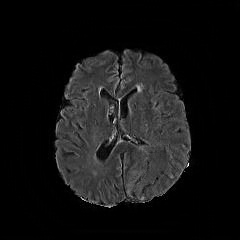

We observe that the generated normal-looking from ANT-GAN can also be used to directly segment the image, since the only difference between a synthesized normal-looking image and its real abnormal counterpart is region with the lesion. To illustrate this, we calculate the absolute difference between x𝑥x and 𝒢A2N(x)subscript𝒢A2N𝑥\mathcal{G}_{\rm{A2N}}(x) and show the segmentation after binary thresholding at 0.1 in Figure 9.

Refer to caption

(a) Tumor x𝑥x

(b) 𝒢A2N(x)subscript𝒢A2N𝑥\mathcal{G}_{\rm{A2N}}(x)

(c) Prediction

(d) Label

Figure 9: Example segmentation obtained by taking the absolute difference between the real tumor MRI x𝑥x and the generated normal-looking MRI 𝒢A2N(x)subscript𝒢A2N𝑥\mathcal{G}_{\rm{A2N}}(x), after binarization at a preset threshold.